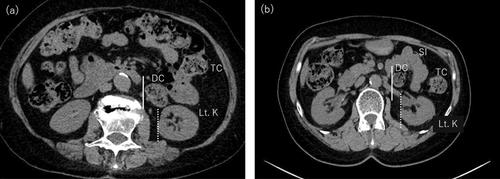

Two patients with pelvic organ prolapse underwent robot-assisted sacrocolpopexy. In both cases, the sigmoid colon was displaced to the right, making exposure of the sacral promontory from the right side of the mesosigmoid challenging. Therefore, the sacral promontory was exposed and mesh fixed from the left side of the mesosigmoid. The postoperative course was uneventful.